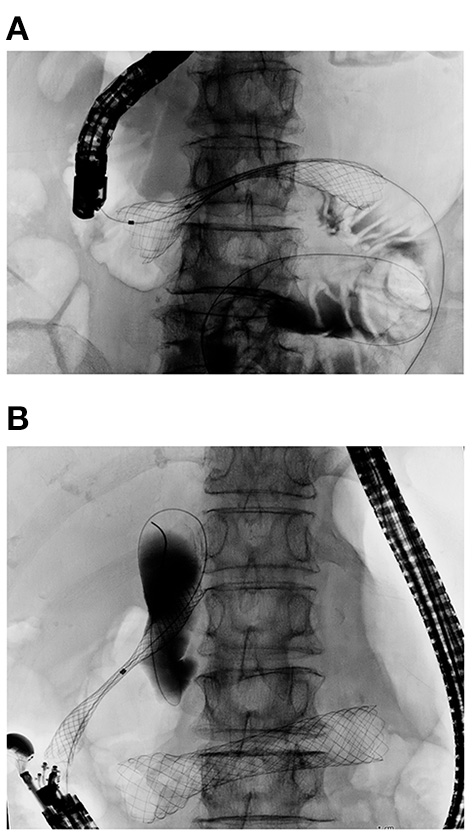

There are three types of nonsurgical biliary interventions: (i) endoscopic transpapillary biliary drainage (ETBD) by endoscopic retrograde cholangiopancreatography, (ii) percutaneous biliary drainage, and (iii) endoscopic ultrasound-guided biliary drainage (EUS-BD) (Figure 6). A meta-analysis (80) also proposed that ETBD can be recommended as a first-line treatment for cases with coexisting biliary obstruction because of its lower AE rate compared to percutaneous biliary drainage or EUS-BD (80).

Figure 6

Double stenting procedure for concurrent biliary and duodenal obstruction. (A) Duodenal stent placed first for D3 obstruction. (B) EUS-CDS was carried out after full expansion of the duodenal stent to avoid duodenobiliary reflux. A SEMS was inserted into the common bile duct and deployed in the proper position.